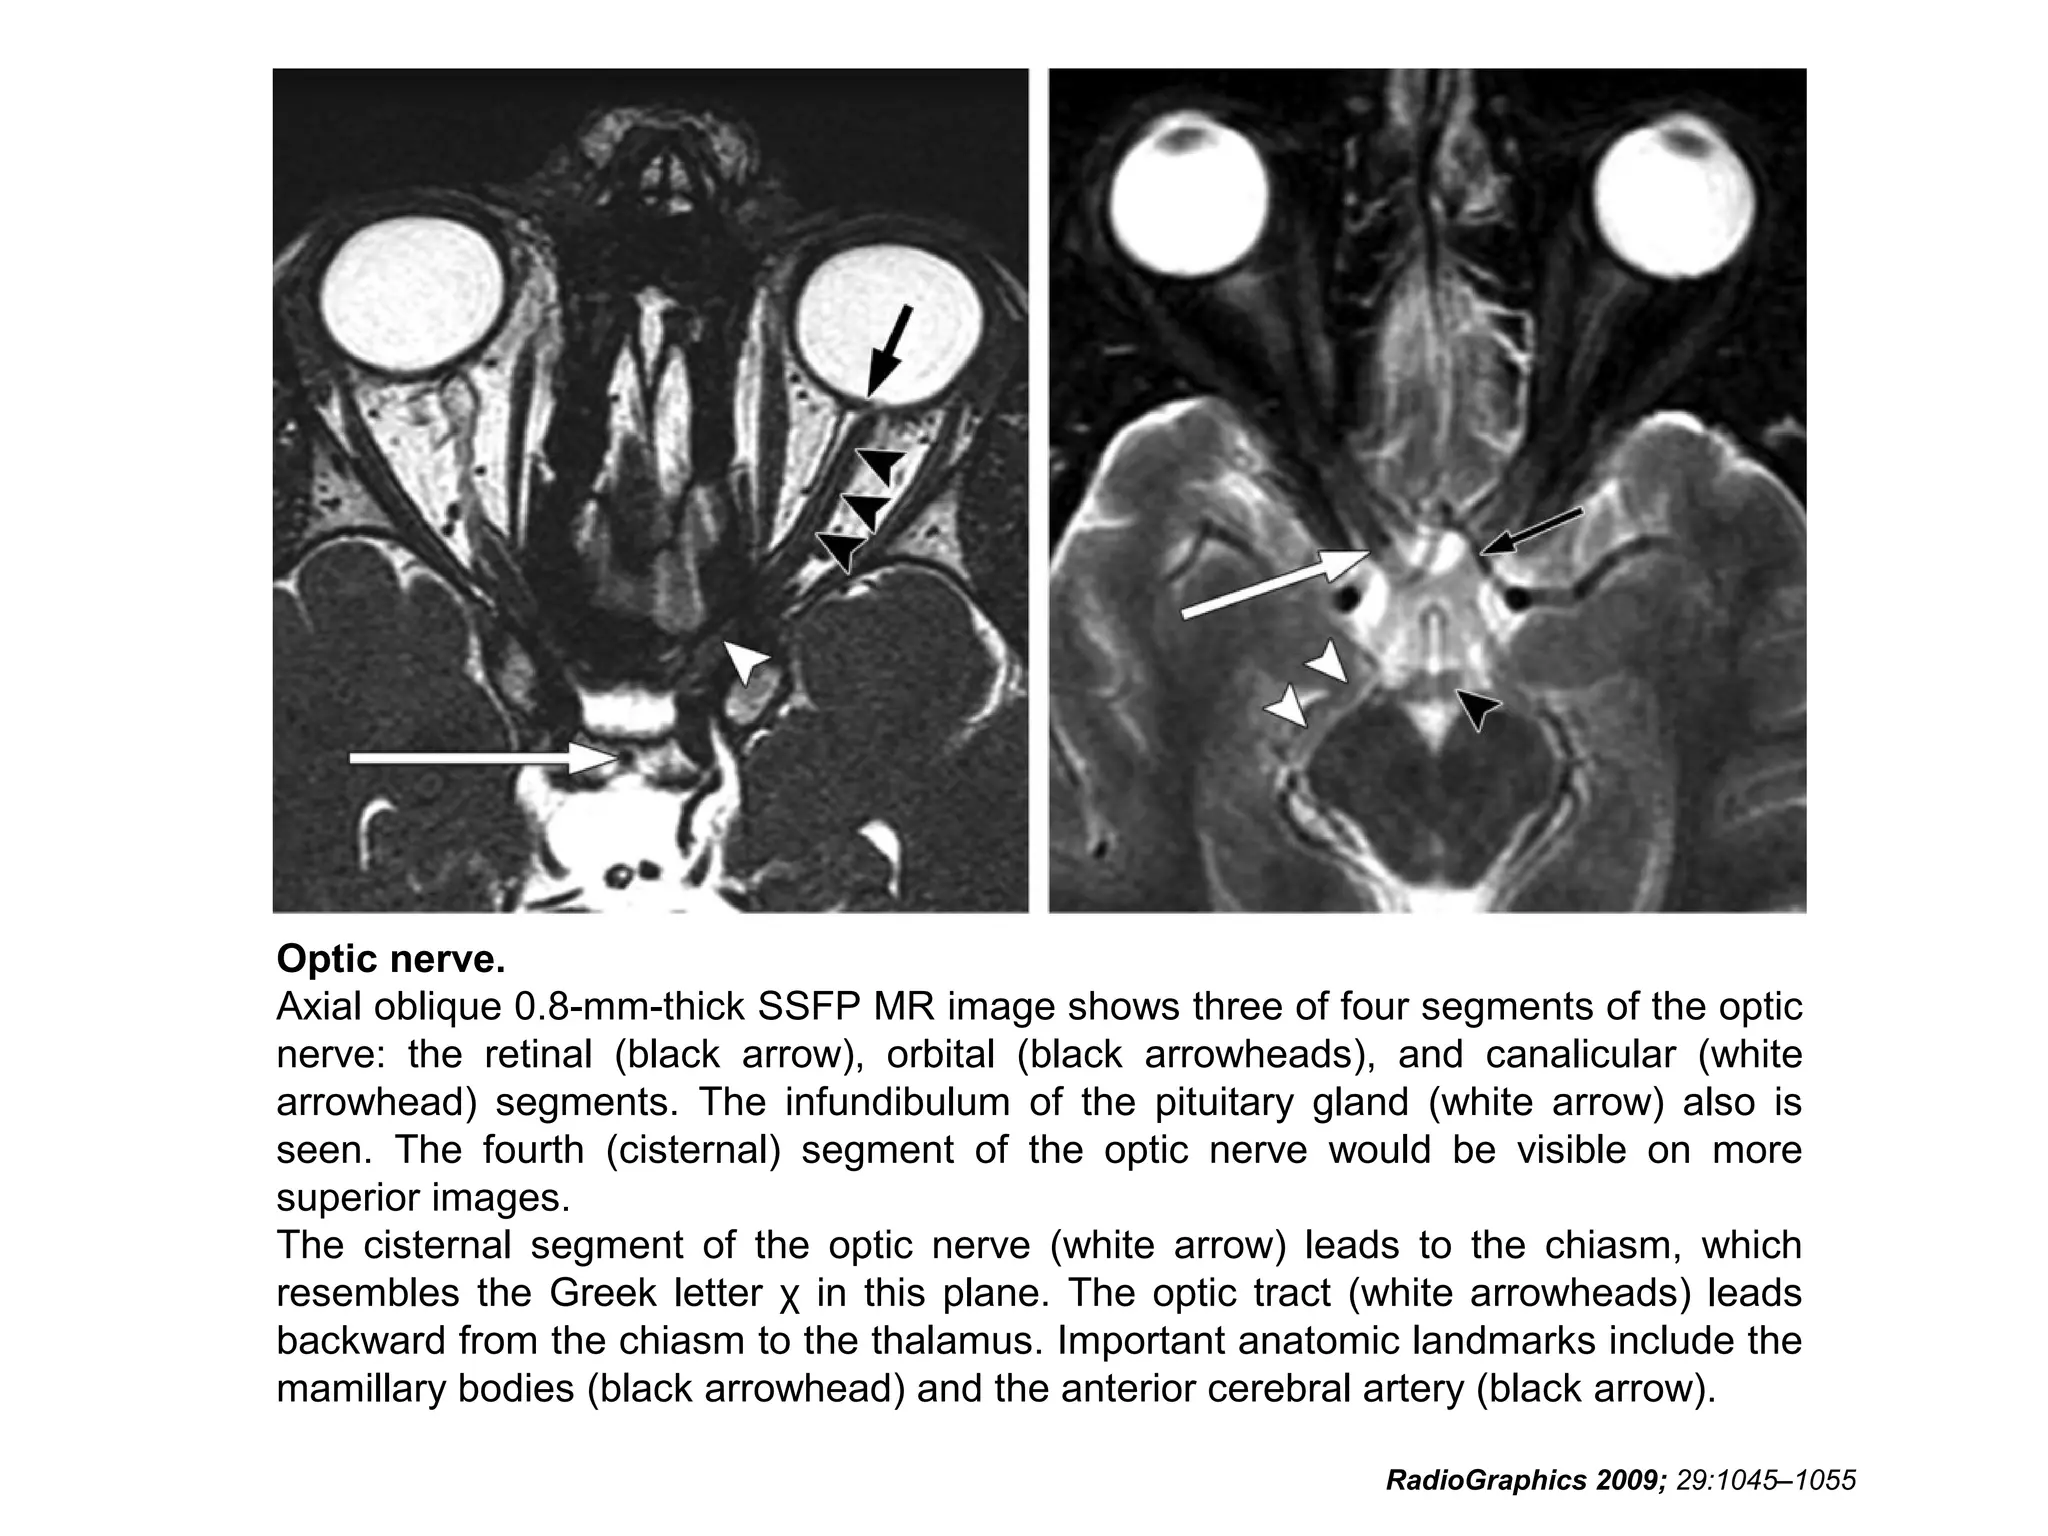

Cranial Nerve II:

The Optic Nerve

• Like the olfactory nerve, the optic nerve is a white-matter tract

without surrounding Schwann cells.

• It includes four anatomic segments: retinal, orbital, canalicular,

and cisternal.

• The retinal segment leaves the ocular globe through the lamina

cribrosa sclerae (the optic foramen of the sclera).

• The orbital segment, which is surrounded by a dural sheath

containing CSF, travels through the center of the fat-filled orbit.

• The canalicular segment is the portion that lies in the optic canal,

below the ophthalmic artery. This segment of the nerve is frequently

overlooked on radiologic images, so it should be specifically sought

when imaging for vision loss.

• Finally, the cisternal segment of the nerve can be visualized in the

suprasellar cistern, where the nerve leads to the optic chiasm. The

anterior cerebral artery passes over the superolateral aspect of the

cisternal segment of the nerve.

RadioGraphics 2009; 29:1045–1055

• Key anatomic landmarks in the suprasellar cistern

include the infundibulum (stalk) of the pituitary gland, the

anterior cerebral artery, and, posterior to the chiasm, the

mamillary bodies.

• The optic nerve terminates at the optic chiasm, where

the two nerves meet, decussate, and form the optic

tracts.

• The optic tracts travel around the cerebral peduncles,

after which most axons enter the lateral geniculate body

of the thalamus, loop around the inferior horns of the

lateral ventricles (Meyer loop), and enter the visual

cortex in the occipital lobe.

Optic nerve.

Axial oblique 0.8-mm-thick SSFP MR image shows three of four segments of the optic

nerve: the retinal (black arrow), orbital (black arrowheads), and canalicular (white

arrowhead) segments. The infundibulum of the pituitary gland (white arrow) also is

seen. The fourth (cisternal) segment of the optic nerve would be visible on more

superior images.

The cisternal segment of the optic nerve (white arrow) leads to the chiasm, which

resembles the Greek letter χ in this plane. The optic tract (white arrowheads) leads

backward from the chiasm to the thalamus. Important anatomic landmarks include the

mamillary bodies (black arrowhead) and the anterior cerebral artery (black arrow).